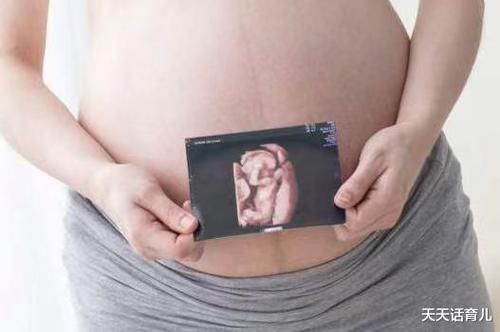

胎儿排畸检查

四维彩超是比较清晰的一种检查,可以看到胎儿的面部、四肢以及心脏等情况,通过体表检查,可以看出胎儿有无畸形,也是比较重要的一种排畸检查。